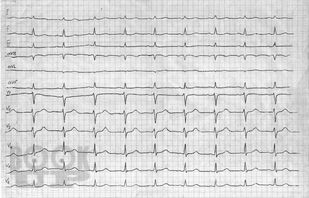

Патологическая физиология. Патология сердечно-сосудистой системы

Структура рабочей тетради, составленной коллективом преподавателей кафедры патологической физиологии ФГБОУ ВО ЧГМА, соответствует тематике занятий по разделу «Патология сердечно-сосудистой системы» дисциплины «Патологическая физиология. Клиническая патофизиология», содержит задания для самоподготовки, ситуационные задачи. Рабочая тетрадь предназначена для подготовки к практическим и лабораторным занятиям и для самостоятельной аудиторной работы студентов, обучающихся по специальностям 31.05.01 Лечебное дело и 31.05.02 Педиатрия.